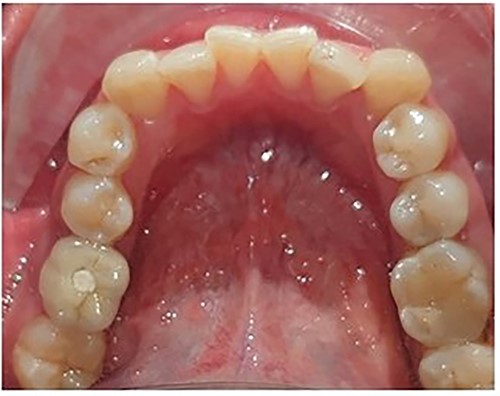

The patient presented with a Class I skeletal relation, mild proclination of the anteriors and occlusal contacts. On examination, she was found to have a normal overjet, crowding in the maxillary arch, supra-erupted maxillary left first molar and missing mandibular first and third molars. The maxillary first molar had supra-erupted by >4 mm beyond the occlusal plane, thereby reducing the space available for placement of a lower prosthetic crown.

Maxillary molar intrusion 4 mm above the occlusal plane (Fig. 3).